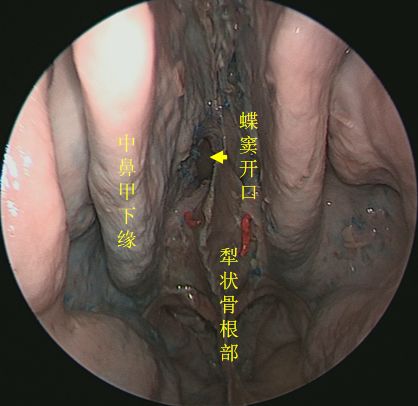

↑ 去除左侧中鼻甲,抵近观察左侧蝶筛隐窝

↑ 去除双侧筛窦,观察完整蝶窦前壁